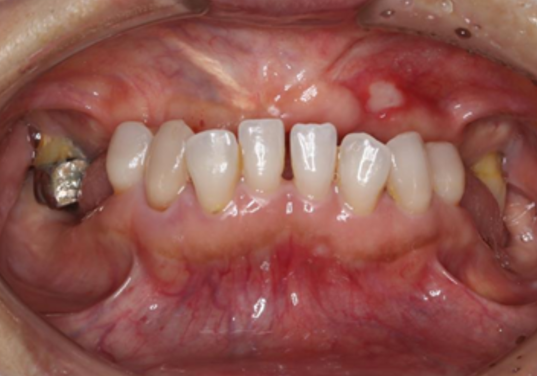

症例